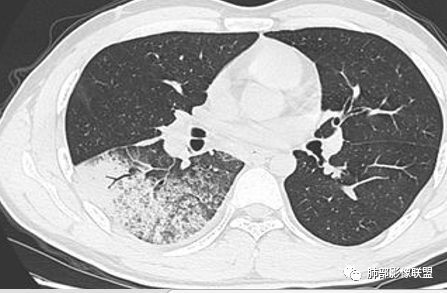

青年男性,急性病程,首次CT实变周围伴磨玻璃,边缘模糊,4天后病变明显进展大片状实变,边缘部可见磨玻璃影,内见支气管气象。考虑感染性病变,支原体?病毒?

初次右肺下叶斑片状磨玻璃及实变影,4天后复查明显进展,大片实变及磨玻璃,细网格,下叶近段支气管壁增厚,扩张,无胸腔积液,考虑社区获得性肺炎,病毒性肺炎?

青年男性,4天前受凉咳嗽咳痰,影像表现:第一次ct示右肺下叶斑片影,边缘模糊,有晕征,第二次ct示右肺下叶大片状影,部分实变,边缘见磨玻璃模糊影,以胸膜下分布为主,与胸膜呈糊墙改变,两次复查,较前进展,白细胞不高,中性粒偏高,常规考虑感染性病变,病毒性肺炎可能,其他不排,建议病原体等相关检查。

青年男性,咳嗽咳痰发热4天,急性起病,抗感染治疗效果不佳,白细胞计数降低。第一次CT:右下叶斑片实变影伴磨玻璃影,边缘模糊。4天后复查CT:病变快速进展,右下叶大片实变影,内可见支气管充气征,边缘模糊,可见腺泡结节,叶间裂膨隆。考虑:大叶性感染,叶间裂膨隆,肺克?军团、病毒性肺炎无法除外。

患者青年男性,急性起病且使用抗菌素治疗后仍快速进展,主要症状表现为咳嗽、咳痰、畏寒、发热4天。血常规:白细胞及淋巴细胞降低。胸部CT:右下肺背段+基底段可见实变+GGO+支气管充气征,病灶位于胸膜外带下比靠近肺门处重,支气管壁未见增厚。诊断首先感染性疾病,腺病毒性肺炎可能性最大。